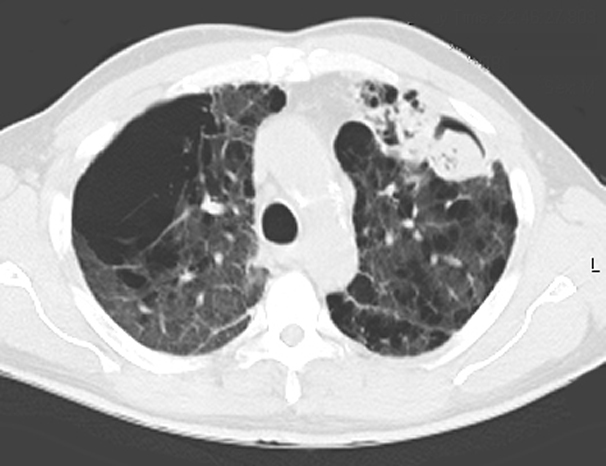

Визуализация и диагностика неинвазивного аспергиллеза с помощью КТ

Раздел: Необычные решения